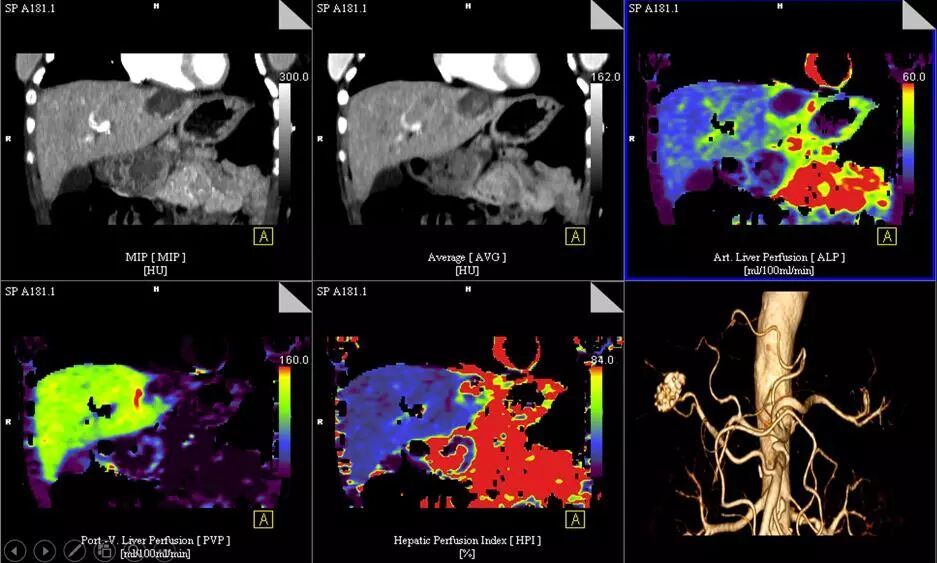

6.低劑量全臟器灌注和動態(tài)血流成像:

超大范圍80厘米功能成像,只需要一次平掃的輻射劑量,既可完成一站式全器官灌注掃描(神經(jīng)、體部、心?。┖蛣討B(tài)血流評估,更安全而全面的獲取形態(tài)學(xué)和功能學(xué)信息。

△肝臟5D灌注,本底輻射劑量,取代傳統(tǒng)多期相掃描